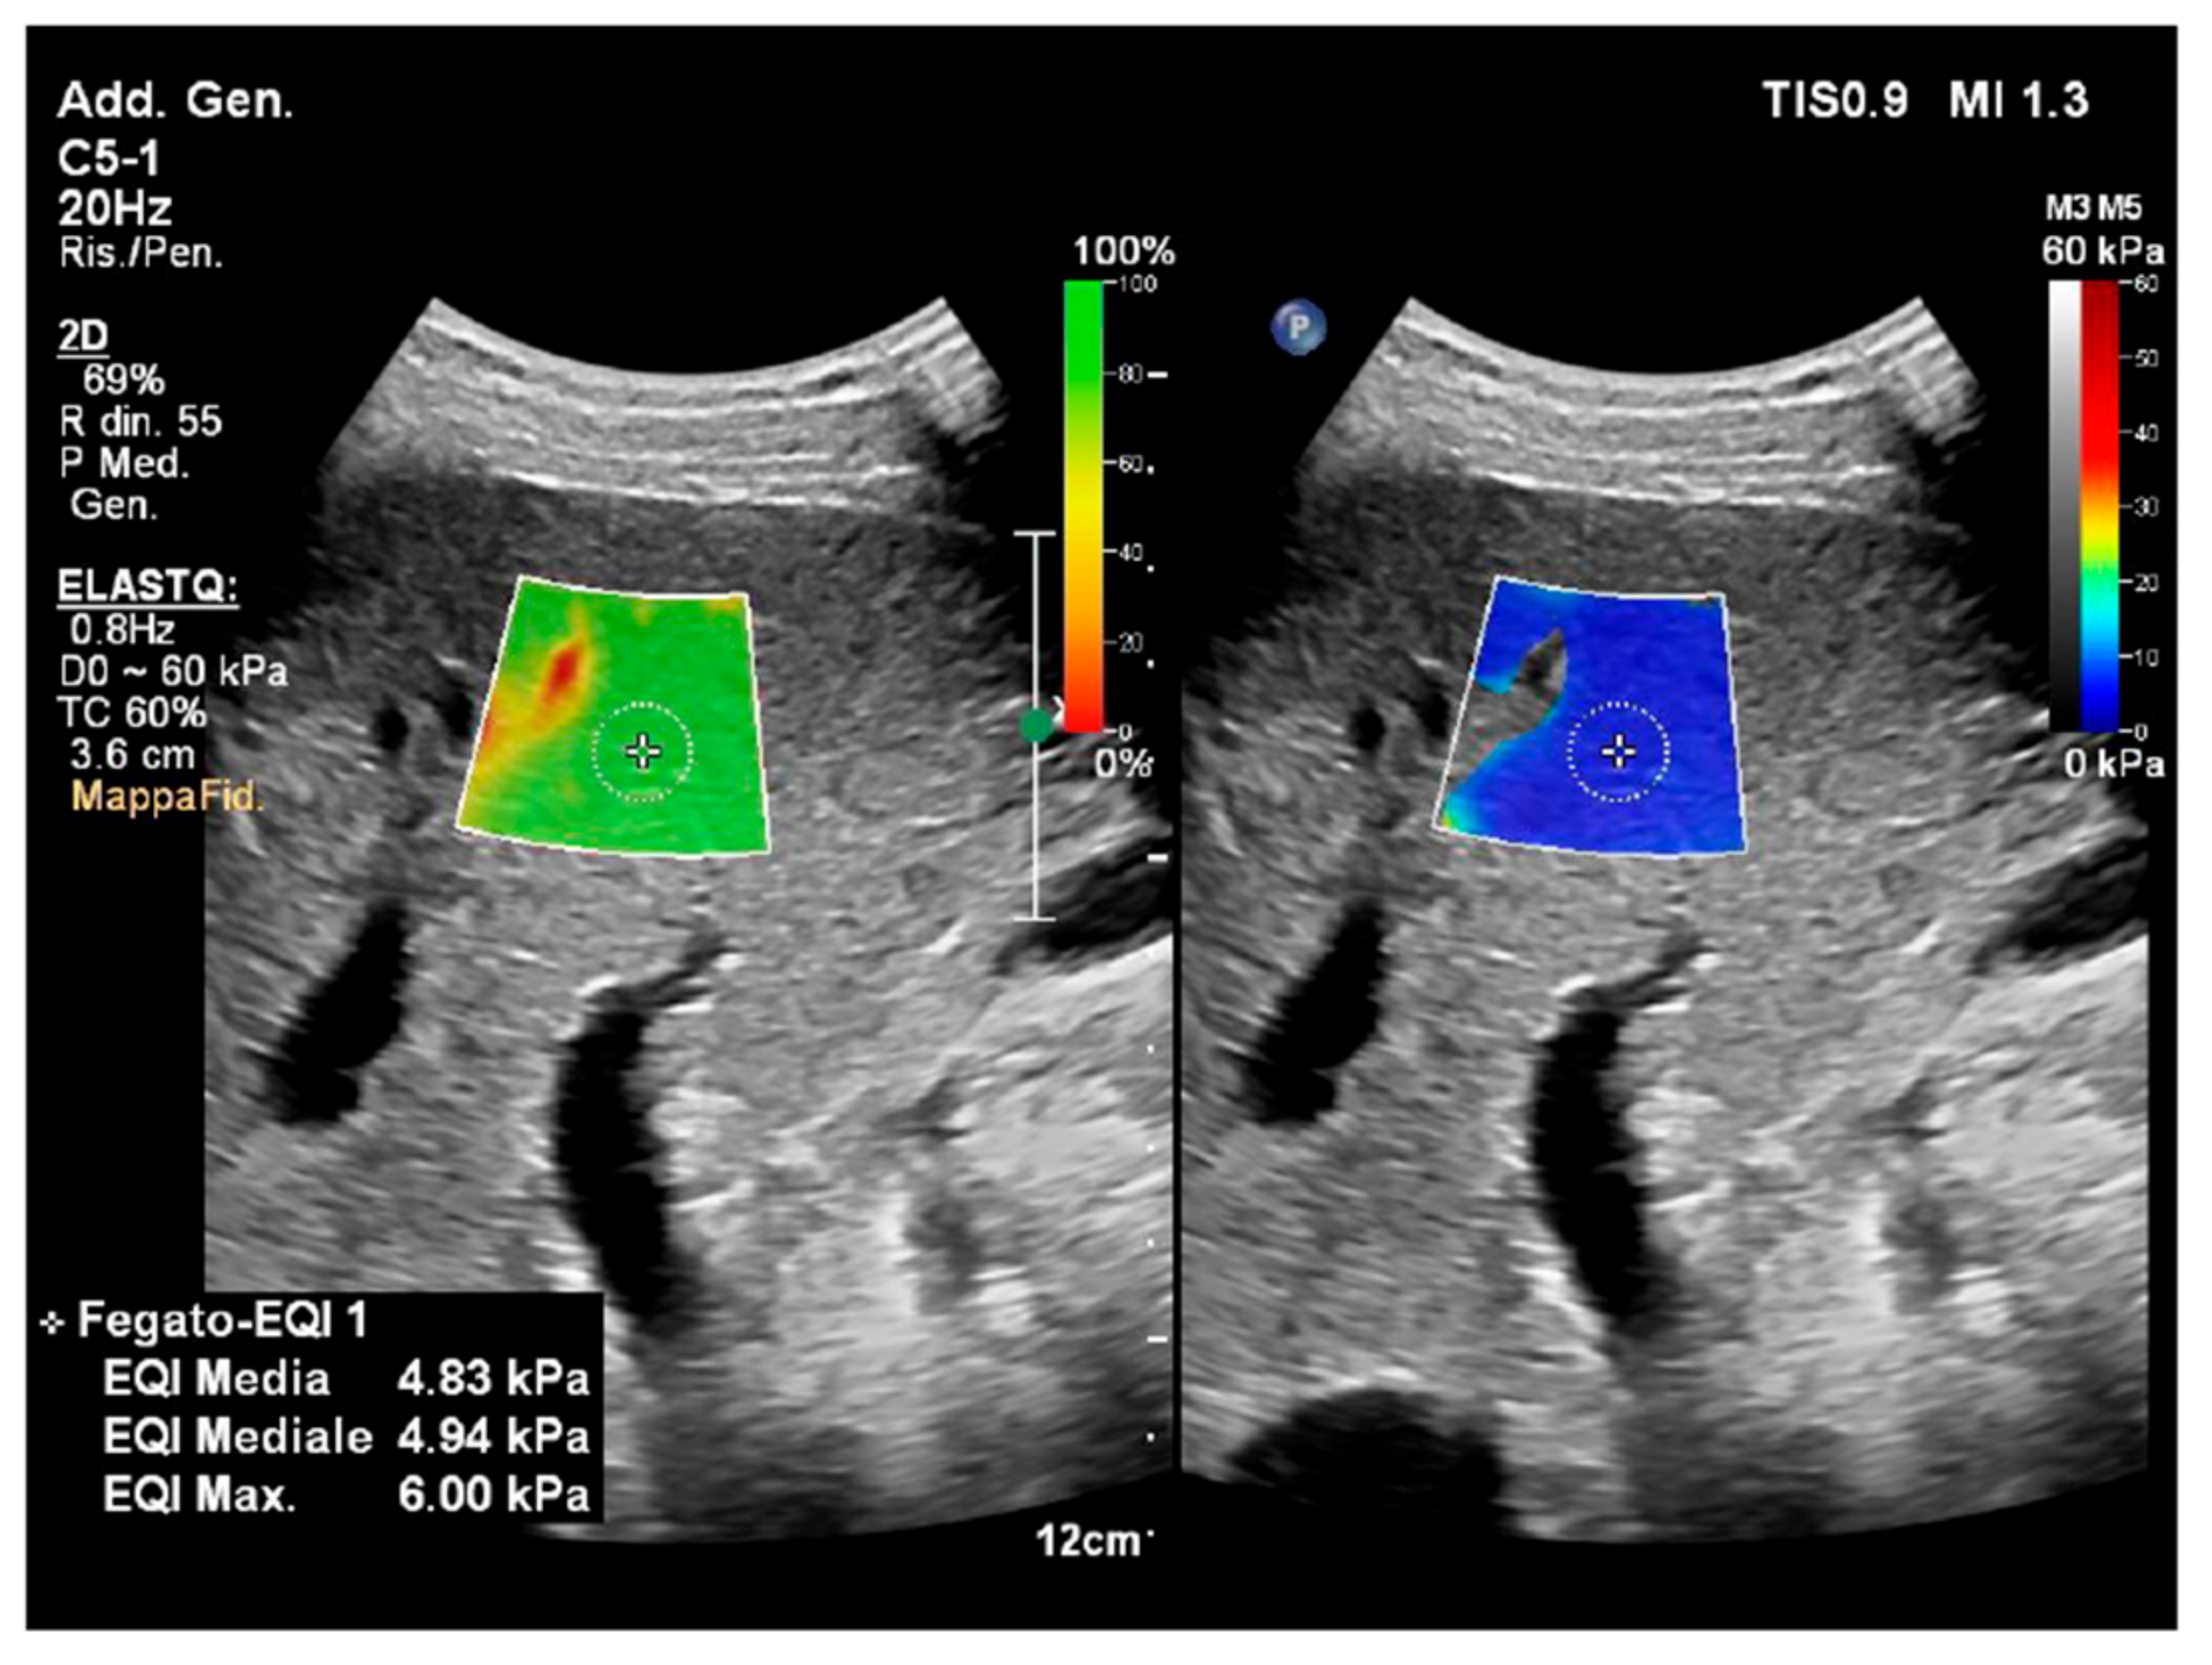

4.1. Liver

- Yazaki, T.; Tobita, H.; Sato, S.; Miyake, T.; Kataoka, M.; Ishihara, S. Combinational elastography for assessment of liver fibrosis in patients with liver injury. J. Int. Med. Res. 2022, 50, 3000605221100126. [Google Scholar] [CrossRef] [PubMed]